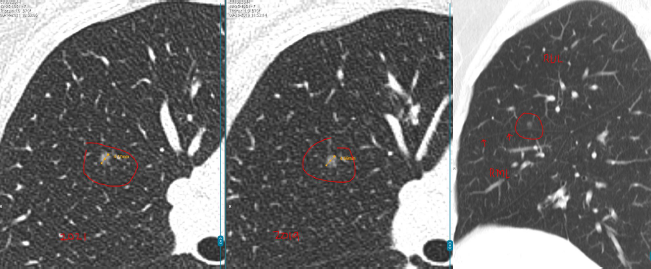

数年前,孙女士(化名)在一次体检中意外查出双肺多发结节:

左肺下叶:2枚实性结节,约5mm、3mm

右肺上叶:1枚磨玻璃结节,约4mm

每年复查,她都紧张得睡不着。好在3个结节都一直很“老实”,没变大。可四年后的一次CT复查,让她的心又提了起来:

左肺结节无变化,但右肺的4mm结节密度增高了,还又新添了一颗3mm的磨玻璃结节。

教授指出,右肺那颗4mm的磨玻璃结节虽然密度略有增加,但变化非常小,还不足以判断为恶化。

而左肺的两枚实性结节稳定了三年多,良性可能性超过99%。另外舌叶可见线状影,较前稳定,符合炎性、瘢痕特征。

至于新出现的那颗3mm磨玻璃结节,教授认为它也很“温和”,更像是一种暂时的炎性反应,有可能过段时间就自行消失了。